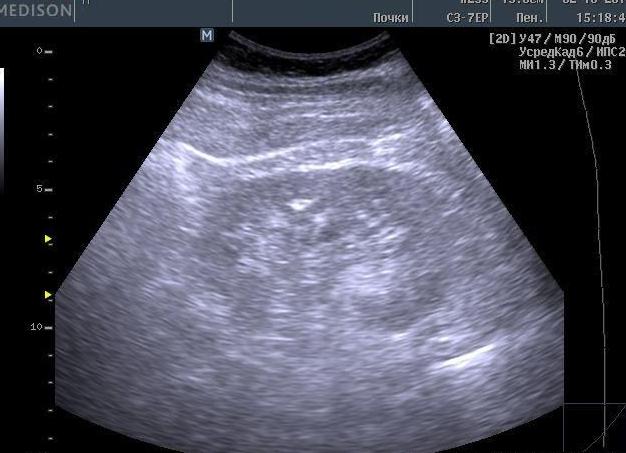

Микроскопия осадка мочи – анализ, помогающий определить возможные отклонения от норм, что указывает на наличие болезни. Микроскопический тест выявляет количественное содержание органических и неорганических элементов. Если показатели не соответствуют нормальным значениям, может потребоваться дополнительное более детальное исследование мочи.